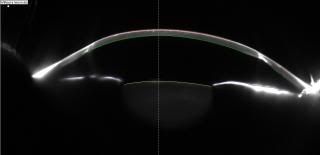

Below are the Pentacam scans of my grafts taken in 2011, right graft then was 22 years and the left was just getting ready to celebrate its 21st birthday. When these were taken I had already been seeing through someone elses corneas for longer than I had seen out of my own and both grafts are still going strong!

You can see that it appeasr i am looking up but that is just the orientation of the picture, but you can clearly see a white vertical line which is the scar tissue where the graft joins to the old cornea. "New" cornea is highlighted with a red line on top and a green line below as this was used by the consultant to get an idea of how thick the graft is. The horizontal line is the iris and the smudge like a bowl with the yellow line on top is the lens of the eye.

LEFT

RIGHT